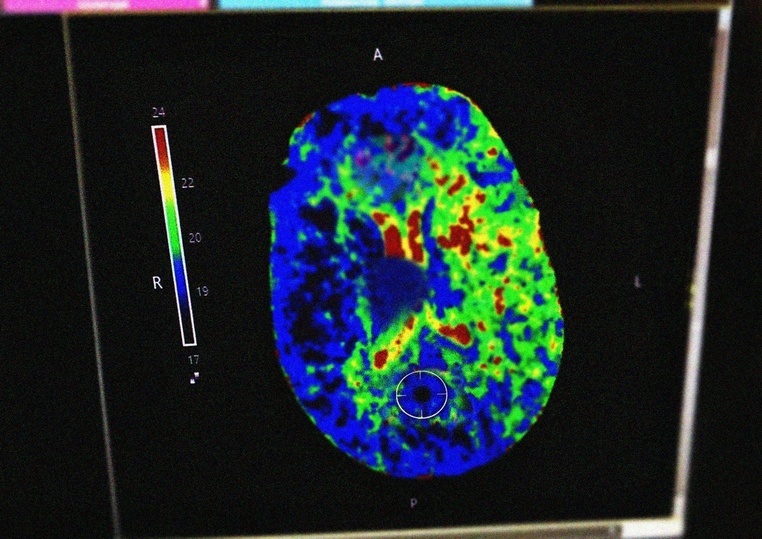

Как пояснил заведующий отделением ОНМК Олег Сорокин, в подобных случаях применяется тромболитическая терапия. Этот метод направлен на растворение тромба, который вызывает нарушение кровообращения, и восстановление кровотока. По его словам, процедура проводится исключительно в условиях стационара и только в первые 3–4,5 часа после появления симптомов.